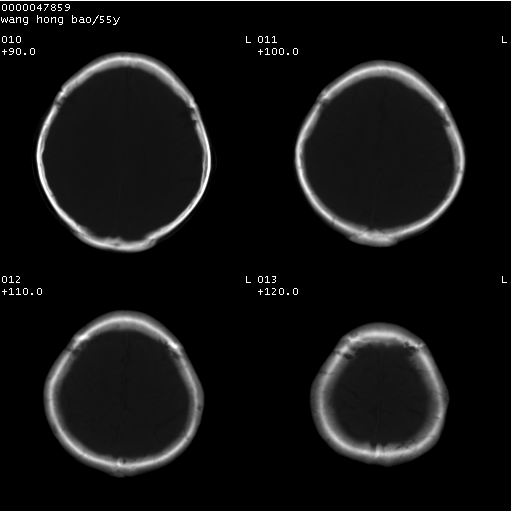

以下是引用dyqct在2008-5-3 23:36:00的发言:[br]桥前池区可疑蛛网膜囊肿。其它未见明显异常。建议做mri。

以下是引用qiushi在2008-5-4 10:10:00的发言:[br]鞍上池前缘突出影为双侧额叶直回;箭头所指为双侧正常之人字缝.[br]桥前池区可疑表皮样囊肿或蛛网膜囊肿,必要时mri

以下是引用zjzjr在2008-5-4 14:50:00的发言:[br]桥前池区可疑蛛网膜囊肿。其它未见明显异常。建议做mri。